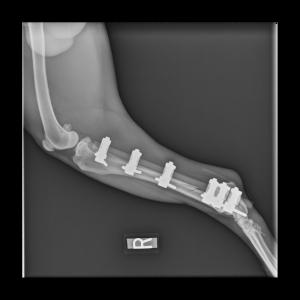

Patient with a Sliding Humeral Osteotomy (SHO).